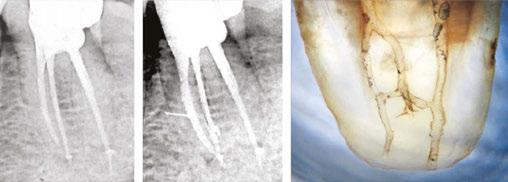

6 mm; and when the bulb is compressed, the tip will expand to 6 mm. The expansion of the bulb and tip act like a periodontal scaler but within the root canal, hence scraping and dislodging all the debris attached to the root canal walls, namely biofilm and stubborn gutta-percha tags in cases of retreatment. It is more effective than passive ultrasonic irrigation in reducing biofilm and the remaining root canal filling.9,10 This instrument comes in two tip sizes, a No. 25 and a No. 30. The No. 30 is also known as the Finisher-R, indicating its usefulness in retreatments. The No. 30 is slightly stiffer than the No. 25, making it an ideal wire to whip and detach stubborn gutta percha.

Finally, the XP-3D Finisher causes turbulence of the irrigant, maximizing the anti-microbial effect and therefore achieving deep disinfection in a safe and anatomical fashion.

Once inside the canal, the XP-3D Finisher is rotated for 60 seconds at 1000 rpm, moving it up and down at an amplitude of 7 mm to 8 mm in order to adequately spread the action of the tip and the bulb. The canal has to be filled with NaOCl or Triton and should be minimally prepared to a size ISO25 for the No. 25 Finisher and to a size ISO30 for the No. 30 Finisher.

The XP-3D Finisher is indicated to be used (Figure 5):

1. After conventional NiTi instrumentation

2. After XP-3D Shaper+ especially in oval canals

3. In retreatment cases

4. In special anatomical cases such as internal resorptions, dens in dente, and immature roots

With the XP-3D Finisher in a clinician’s armamentarium, eliminating biofilm and maximizing disinfection is now possible in a minimally invasive fashion.

Figure 5: The XP-3D Finisher can be used in many situations. Its ability to expand and scrape the root canal walls make it an ideal instrument to remove biofilm and previous root canal filling as well to adapt and clean special anatomical cases such as a dens in dente